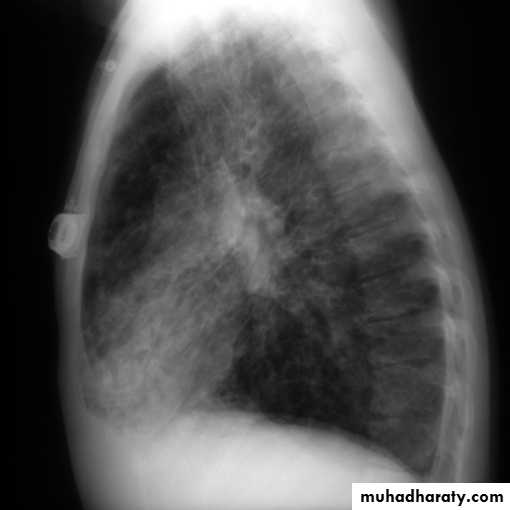

Lateral view

IndicationsAnterior mediastinal mass

Encysted pleural fluids

Posterior basal consolidation